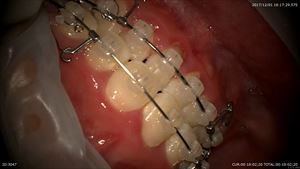

3つめは矯正の男の子17歳

抜歯して当初は出っ歯ちゃんでしたがなんと8ヶ月で治ってきました。抜歯したスペースも閉じています。デーモンシステム最高です。